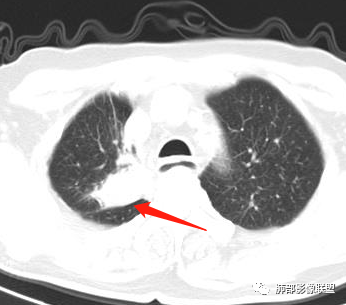

男性,69岁 反复咳嗽2年余,加重3天入院。CT示右肺上叶尖段不规则实变影,周边伴条索影,支气管未见明显堵塞,增强不均匀强化,考虑为恶性,腺癌可能

男,69,反复咳嗽2年,加重3天入院,右肺上叶软组织密度肿块影,边界尚清晰,边缘见毛刺及胸膜牵拉,右肺上叶支气管壁增厚,增强扫描不均匀性强化,考虑腺癌可能,鉴别炎性病变。

结合本病例,老年男性患者,慢性病程,急性加重,无吸烟史,影像学表现为右肺上叶尖后段斑片实变密度影,整体边界清晰,边缘平直收缩为主,周边散在纤维条索影,内部见支气管内粘液栓,血管影走形正常,没有明显破坏,增强扫描明显强化,缺乏典型分叶毛刺、胸膜改变,病灶也未显示清楚的磨玻璃勾边,病灶大而肺门纵隔未见肿大淋巴结,综合考虑慢性炎性肉芽肿可能性大。但恶性,结核能完全排除吗?我想对临床医生来说还是有很大考验的。